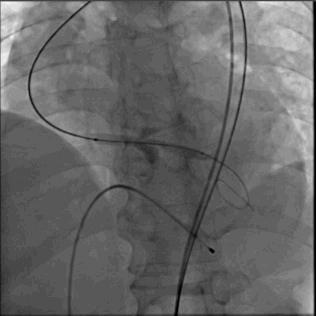

3.主动脉弓弯折扭曲,建议使用 snare

输送系统到位

圈套器snare 协助输送系统安全准确达到预计区域,猪尾主动脉根部造影确认系统和窦底的相对位置,调整重置锚定区

瓣膜释放

VenusA 26支架,高位 释放

1.ring释放到mark点往下2mm处,造影观察位置(此时仍可以调整位置)

2.瓣膜释放瓣架打开 瓣架开始附着在钙化区 高速起搏 血压下降 系统保持相对稳定

3.支架开始贴壁,血压开始恢复,支架下部锚定区固定,停止起搏 。

4.造影观察冠脉情况 瓣叶运动工作 是否PVL 返流等

5.完全释放瓣膜

6.猪尾导管拉回 放置新的人工瓣膜工作区域上方造影

7.瓣膜支架未完全打开,返流 PVL均存在,决定后扩

8.支架展开形态良好 返流大幅度减少

9.仅在钙化严重,窦交界区域有PVL,符合术前预估